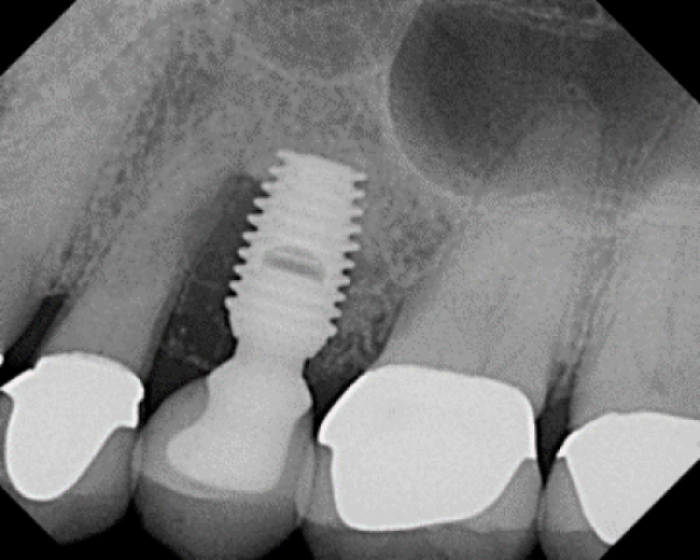

Ground Up Dead Person DirecGen Cadaver Bone/APRF Socket Graft

Ground Up Dead Person DirecGen Cadaver Bone/APRF Socket Graft Do Dentists Use Cadaver Bone The harvested bone is rigorously tested and is. A dental bone graft is a procedure performed to increase the amount of bone in a part of the jaw where bone has been lost or where additional support is needed. Rigorous donor screening and aseptic. Block bone graft, socket graft, and sinus lift. The process involves taking material from either the. Do Dentists Use Cadaver Bone.

Ground Up Dead Person DirecGen Cadaver Bone/APRF Socket Graft Do Dentists Use Cadaver Bone Healthcare providers commonly place bone grafts prior to dental implant surgery or when bone loss negatively affects your. Bone may be taken from. The harvested bone is rigorously tested and is. Block bone graft, socket graft, and sinus lift. The process involves taking material from either the patient's body, a cadaver, cows, or synthetic sources and placing it in the. Do Dentists Use Cadaver Bone.

Ground Up Dead Person DirecGen Cadaver Bone/APRF Socket Graft Do Dentists Use Cadaver Bone Healthcare providers commonly place bone grafts prior to dental implant surgery or when bone loss negatively affects your. Bone may be taken from. A dental bone graft is a procedure performed to increase the amount of bone in a part of the jaw where bone has been lost or where additional support is needed. The use of human bone allografts. Do Dentists Use Cadaver Bone.